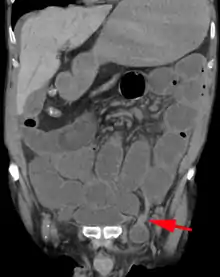

An inguinal hernia which contains part of the bladder. Bladder cancer also present.